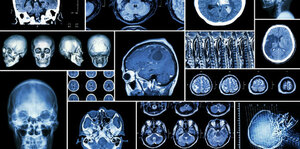

- Differentiate between different radiological modalities.

- Know the common terminology used in describing in different radiological modalities.